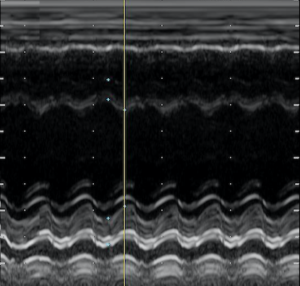

診断

エコー検査により心筋壁の菲薄化、収縮、拡張能の低下

心臓のエコーで心臓の動きが弱くなってしまっていることが確認できる